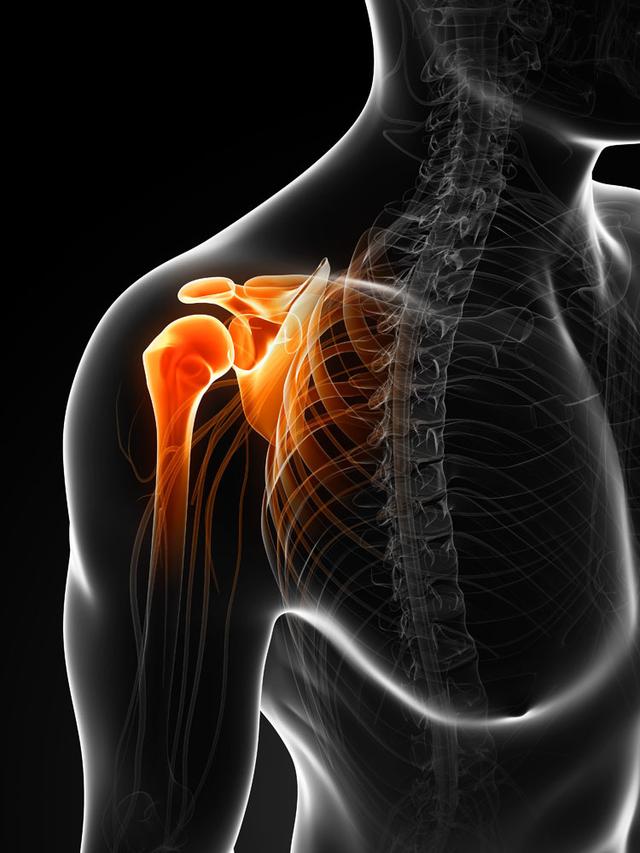

从一方面来说,人类是弱小的,容易生病,容易受伤,但从另一方面来说,人类也是强大的...